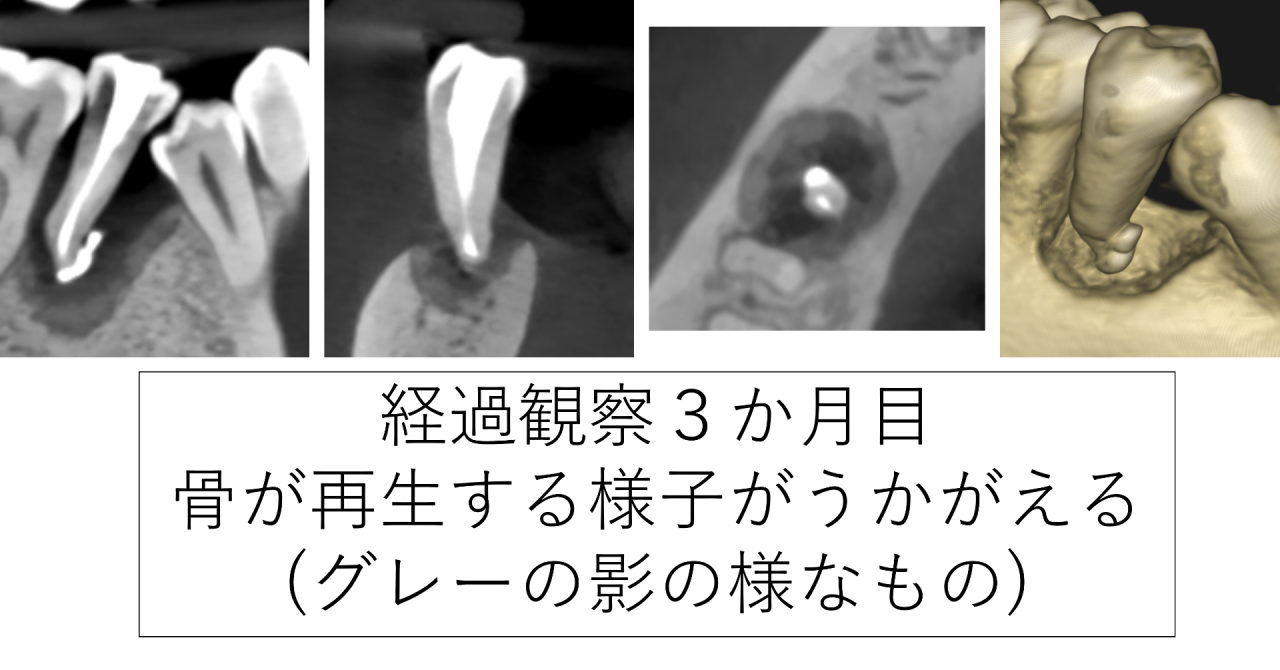

経過観察し、3か月後CTを撮影しました。すると、骨が再生してきている様子がうかがえました。歯科衛生士による歯磨き指導も行っており、歯ぐきに歯石が再度付くことを予防します。